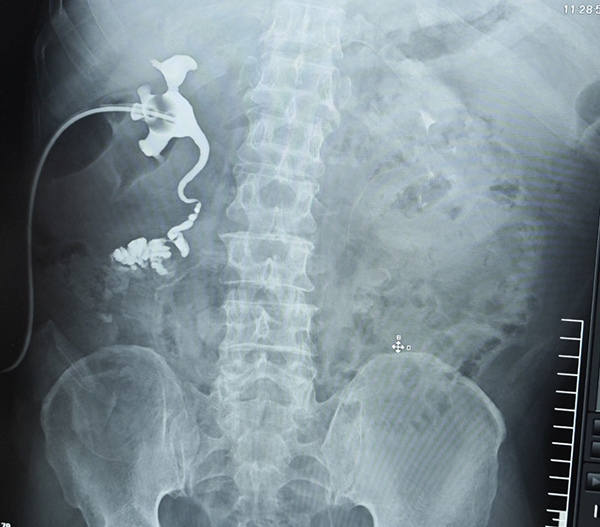

患者术前影像结果显示